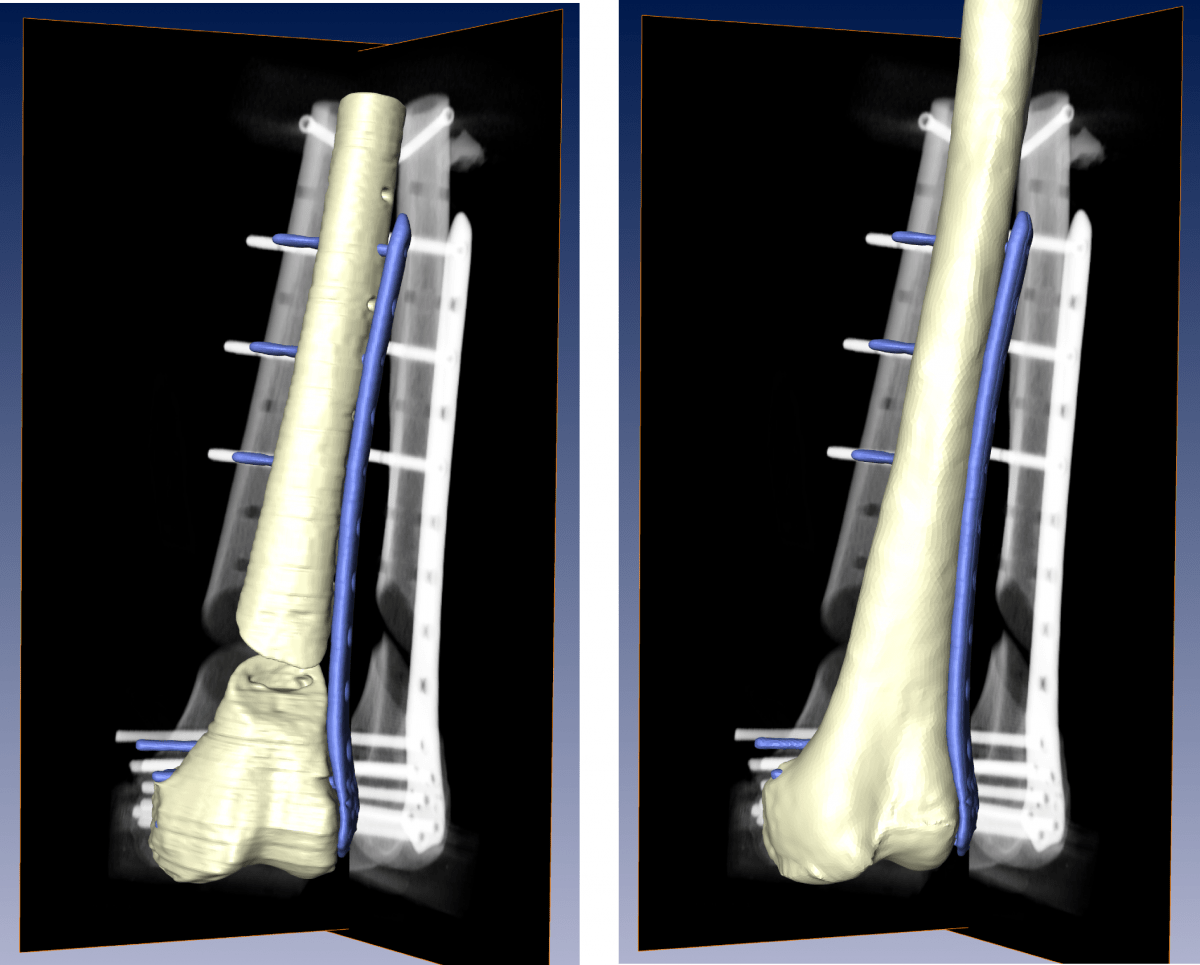

Osteosynthesis Followup from 2D Xrays Zuse Institute Berlin (ZIB) Meaning Plate Osteosynthesis The surgeon exposes the broken bone and screws a. Plate osteosynthesis is one treatment option for the stabilization of long bones. Plate osteosynthesis is a procedure in which the broken parts of the bone are fixed with a plate. Plate osteosynthesis is one treatment option for the stabilization of long bones. We attempted to find an answer to the following. Meaning Plate Osteosynthesis.

From www.intechopen.com